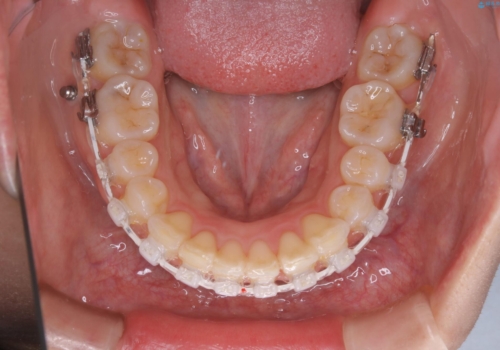

- 審美装置(ワイヤー)

- 前歯のがたつきが気になるとご相談にいらした方です。当初は前歯の部分矯正をご希望されていましたが、全体的に整えることで審美的、機能的な歯並びとなりました。

当初は上顎前歯のみの部分矯正をご希望されていましたが、部分的に前歯のみを並べると出っ歯感がつよくなり、食事もしづらくなる可能性をお伝えしました。全顎的な矯正治療により、審美的、機能的な歯並びとなりました。